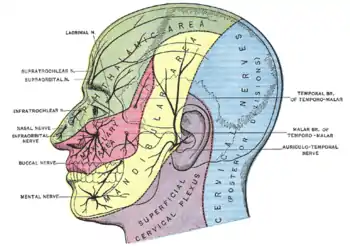

Sensory branches

The ophthalmic, maxillary and mandibular branches leave the skull through three separate foramina: the superior orbital fissure, the foramen rotundum and the foramen ovale, respectively. The ophthalmic nerve (V1) carries sensory information from the scalp and forehead, the upper eyelid, the conjunctiva and cornea of the eye, the nose (including the tip of the nose, except alae nasi), the nasal mucosa, the frontal sinuses and parts of the meninges (the dura and blood vessels). The maxillary nerve (V2) carries sensory information from the lower eyelid and cheek, the nares and upper lip, the upper teeth and gums, the nasal mucosa, the palate and roof of the pharynx, the maxillary, ethmoid and sphenoid sinuses and parts of the meninges. The mandibular nerve (V3) carries sensory information from the lower lip, the lower teeth and gums, the chin and jaw (except the angle of the jaw, which is supplied by C2-C3), parts of the external ear and parts of the meninges. The mandibular nerve carries touch-position and pain-temperature sensations from the mouth. Although it does not carry taste sensation (the chorda tympani is responsible for taste), one of its branches—the lingual nerve—carries sensation from the tongue.

Dermatomes

The areas of cutaneous distribution (dermatomes) of the three sensory branches of the trigeminal nerve have sharp borders with relatively little overlap (unlike dermatomes in the rest of the body, which have considerable overlap). The injection of a local anesthetic, such as lidocaine, results in the complete loss of sensation from well-defined areas of the face and mouth. For example, teeth on one side of the jaw can be numbed by injecting the mandibular nerve. Occasionally, injury or disease processes may affect two (or all three) branches of the trigeminal nerve; in these cases, the involved branches may be termed:

- V1/V2 distribution – Referring to the ophthalmic and maxillary branches

- V2/V3 distribution – Referring to the maxillary and mandibular branches

- V1-V3 distribution – Referring to all three branches

Nerves on the left side of the jaw slightly outnumber the nerves on the right side of the jaw.

Trigeminal nuclei

All sensory information from the face, both touch-position and pain-temperature, is sent to the trigeminal nucleus. In classical anatomy most sensory information from the face is carried by the fifth nerve, but sensation from parts of the mouth, parts of the ear and parts of the meninges is carried by general somatic afferent fibers in cranial nerves VII (the facial nerve), IX (the glossopharyngeal nerve) and X (the vagus nerve).

All sensory fibers from these nerves terminate in the trigeminal nucleus. On entering the brainstem, sensory fibers from V, VII, IX and X are sorted and sent to the trigeminal nucleus (which contains a sensory map of the face and mouth). The spinal counterparts of the trigeminal nucleus (cells in the dorsal horn and dorsal column nuclei of the spinal cord) contain a sensory map of the rest of the body.